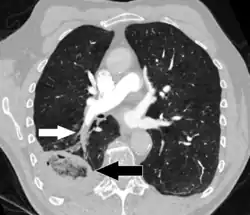

Large saddle embolus seen in the pulmonary artery (white arrows)